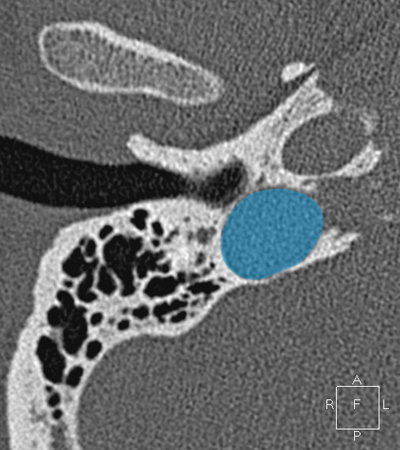

Sigmoid sinus Jugula bulb Horizontal petrous carotid Groove for tympanic (Jacobson's) nerve Facial nerve (f3), mastoid segment Anterious wall of bony EAC (tympanic bone) Mandibular condyle